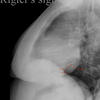

Rigler's sign

to assess LV size

Date: 04/28/2014

Views: 4340